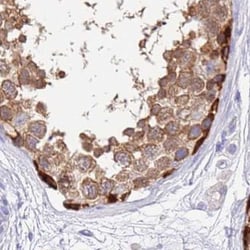

Invitrogen™ STIP1 Polyclonal Antibody

| Immunohistochemistry (Paraffin), Western Blot | |